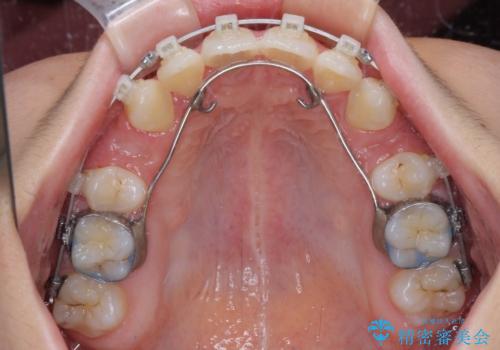

下顎は叢生があったため、上下左右の第一小臼歯4本を抜歯し、更には口元の突出感を大きく改善させるために、上顎臼歯を後方に移動させるための補助装置をしようし、ワイヤー装置にて矯正治療を行うこととしました。